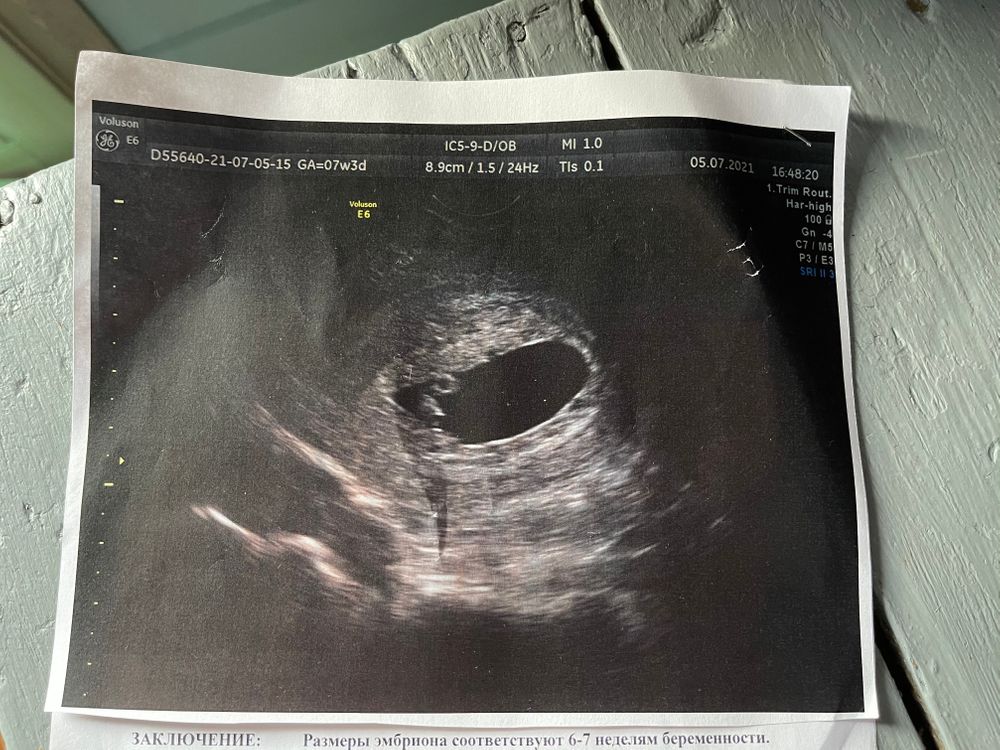

УЗИ 7 нед (+4 дня) нашли человека и сердцебиение 💗

УЗИ, КТГ, доплерУра! Дождалась повторного УЗИ! Теперь все в норме. Нашли эмбриона и сердцебиение. Срок по УЗИ на неделю примерно меньше. В третью беременность тоже была поздняя овуляция, даже очень, тогда срок опаздывал почти на 2 недели.

<напомню: на предыдущем УЗИ при ХГЧ 40000, эмбриона не нашли>

Сделали фото, как сказала врач - для фотоальбома :).